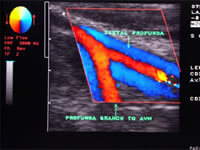

Hacemos tratamiento de varices mediante escleroterapia por microespuma. Realización de Dúplex Venoso y procedimientos guiados por ecografía.